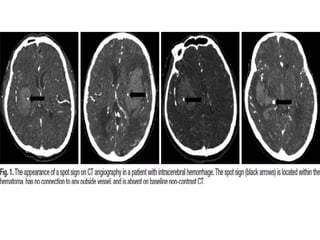

The spot sign was defined according to four criteria :

1.) Serpiginous or spot-like appearance within the margin of a

parenchymal hematoma without connection to an out hematomaside

vessel

2) Contrast density greater than 1.5 mm in diameter in at least one

dimension

3) Contrast density (Hounsfield units, HU) at least double that of the

background hematoma

4) No hyperdensity at the corresponding location on non-contrast CT